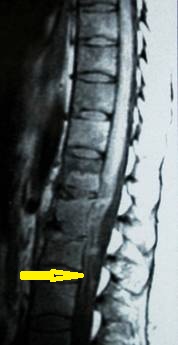

- Figura No 2a

- Figura No 2b

- Figura No 2c

- Figura No 2d

- Figura 2 Texto